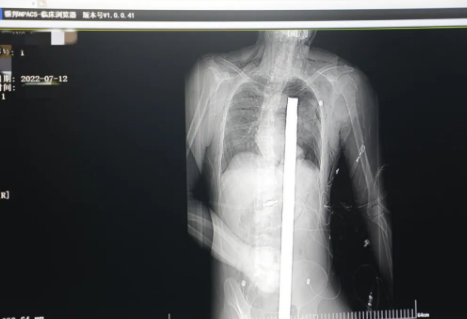

突發(fā)!太疼了,1.2米長的螺紋鋼從男子會陰部垂直穿入胸腔......7月12日下午16時10分,西安一處工地的一名26歲工友,不慎從10多米的高空墜落,不幸的是工地上一根直徑3厘米的螺紋鋼從男子會陰部垂直穿入體內(nèi),工地上的工友們小心翼翼地將連著的鋼筋截斷。情況危急,立即送往西安國際醫(yī)學(xué)中心醫(yī)院急救中心,此時正是下午17時00分。

時間就是生命!此時,西安國際醫(yī)學(xué)中心醫(yī)院展開了一場與生命賽跑的搶救,第一時間開辟綠色通道,急診X光片及CT顯示:異物經(jīng)會陰部貫穿盆腔、腹腔到達左側(cè)胸腔主動脈弓水平。醫(yī)院創(chuàng)傷中心立即啟動應(yīng)急預(yù)案,劉延彤副院長親臨指揮,下午17點48分,當(dāng)患者被送達手術(shù)室,胸外、心外、肝膽外科、胃腸外科,泌尿外科及麻醉科等多學(xué)科專家聯(lián)手對這名工友進行“縱劈胸骨 前外側(cè)開胸探查 氣管及主支氣管修補 肺修補 血胸清除 開腹探查止血 腹膜后及盆腔探查......”手術(shù)。

情況緊急!術(shù)中探查后發(fā)現(xiàn),長120cm直徑3cm的螺紋鋼經(jīng)患者右側(cè)會陰部穿入,傷及直腸,途徑膀胱后方,左側(cè)髂總動靜脈之間傷及左腎后,經(jīng)胰腺后方在肝脾之間穿破膈肌,在下肺靜脈前方穿入左肺穿破氣管及左右主支氣管膜部,止于主動脈弓下水平,穿入體內(nèi)的部分達到75cm。